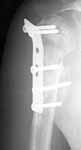

Recently he referred to our physical therapist because of severe limitation of shoulder ROM. The last month he has experienced local pain, increasing with shoulder motions. Also he is disturbed by the prominent implant. Current x-rays attached (images 3,4). The head looks dissolving.

Image 3

Image 4

The current xrays indicate failure of the implant with loosening. I would make sure there was no evidence of infection ( exam, ESR, CRP etc.) . I would agree with implant removal . I think this would be a suitable case for a circular ring fixator and compression, either a standard IIizarov or Taylor Spatial frame would be appropriate. I note from your previous cases that you have a high level of experience with this method.